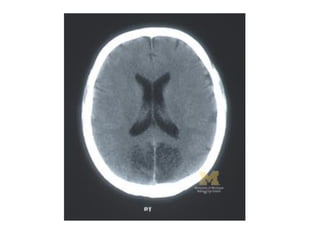

Right superior quadrantanopia >>

temoporal lobe lesion